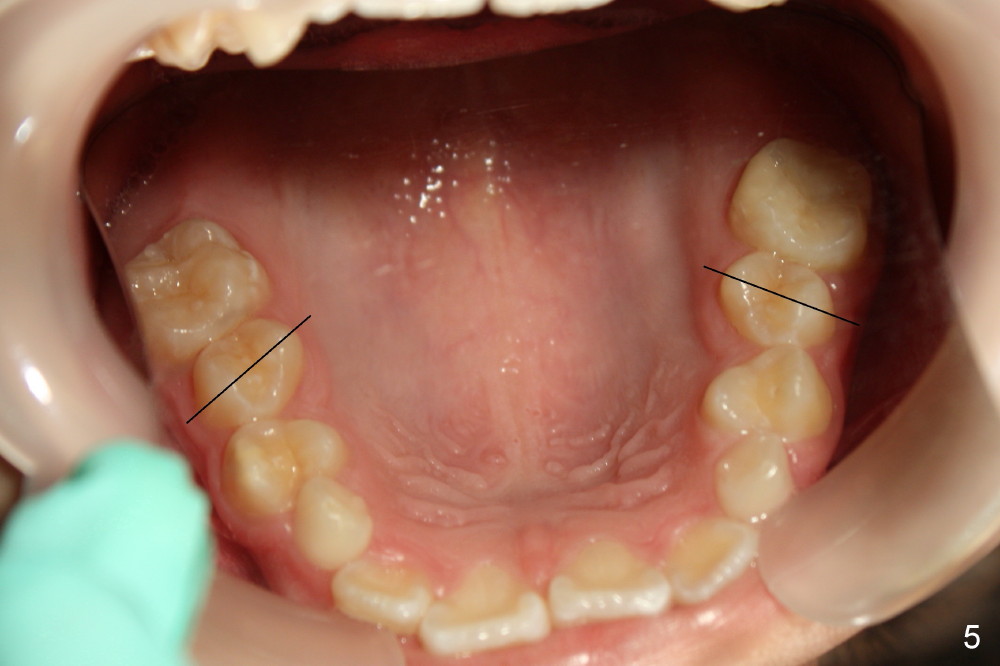

4. Upper 2nd bicuspids (u5s) rotate (Fig.4, 5). Use power chains (Fig.6 different case) to correct rotation quickly to use E space to facilitate u3s eruption (Visit 2)